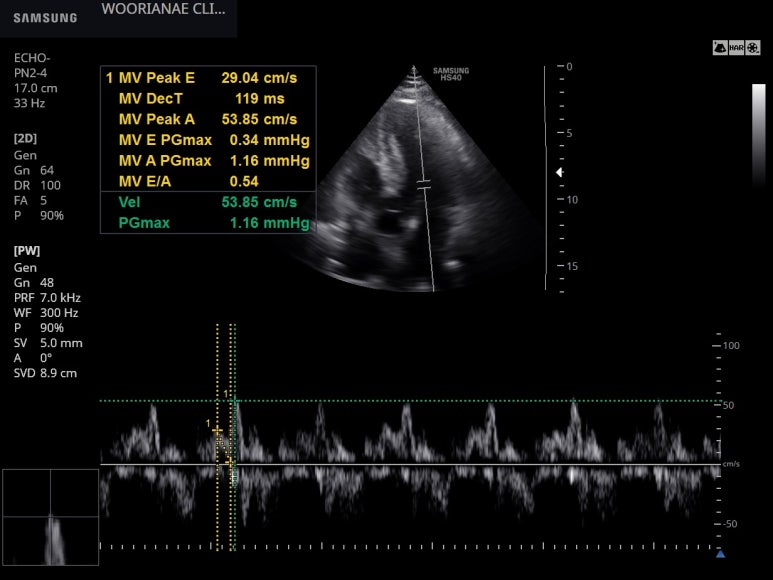

심장초음파 시행함, 기능적 문제는 없음

지난외래 심초음파에서 누락된 이완기 기능에 대해 검사

E/e` 을 보면 정상이다.

그런데 E flow와 e` 이 낮다.

아래 상황과 비슷한 것으로 볼수 있을 것인가? 체중은 아직 평소보다 증가한 상태이나 몇일사이 감소와 더불어 혈관내 순환량이 먼저 감소한것이 아닌지 추정한다.

장정결제 복용 후 체중 감소 --> 탈수 상태에서 E flow의 감소

What is normal mitral flow? 이첨판 혈류 속도는

Flow propagation velocity of mitral inflow (Vp) is evaluated as the slope of the first aliasing velocity during early ventricular filling. It is measured from the mitral valve plane to 4 cm distally into the LV cavity and > 50 cm/s is considered normal.

Reduced Cardiac Output: In cases of volume depletion, peak early (E) and late (A) diastolic filling velocities, along with early diastolic velocities (E`) are significantly reduced.